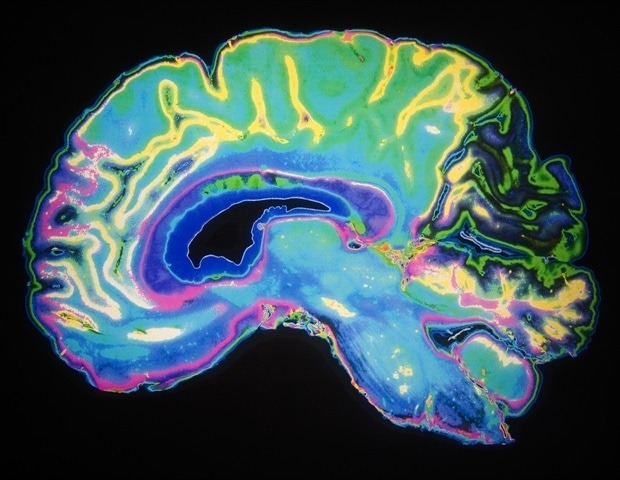

Благодаря точному анализу опухолевой ткани, полученной в результате обширной резекционной операции, и окружающей нормальной ткани головного мозга. В коре головного мозга исследовательская группа обнаружила, что «клетки происхождения», несущие мутацию IDH, уже существуют в ткани мозга, которая невооруженным глазом выглядит нормальной.

Затем исследовательская группа использовала «пространственную транскриптомику» — передовую технологию анализа, которая показывает, «какие гены где работают». одновременно — чтобы подтвердить, что эти исходные клетки с мутациями действительно были глиальными клетками-предшественниками (GPC), расположенными в коре головного мозга.